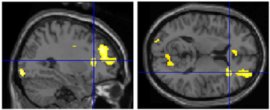

- method: observers naïve to art criticism placed in fMRI while viewing images of Classical and Renaissance sculptures

- stimuli: _________ (original) or modified images

- canonical images all had golden ratio among body parts

e.g., Doryphoros (Polykleitos, c.450-440 BCE)

Doryphoros by Polykleitos

- viewing conditions:

observation (view images “as if they were in a museum”; non-evaluative)

aesthetic judgment

- analyses:

1) compared brain responses to canonical and modified sculptures

2) compared brain responses to beautiful and ugly sculptures (based on observer’s aesthetic judgment)

- findings: canonical images were strongly preferred over modified images

1) canonical sculptures activated right insula (mediates emotions; connects to/from amygdala): evidence for _________ beauty (“I can see why people like that.”)

right insula activity

2) beautiful images activated right amygdala (responds to learned emotional information): evidence for __________ beauty (“I like that.”)

right amygdala activity

- conclusion: both of these non-mutually exclusive processes contribute to appreciation of artwork